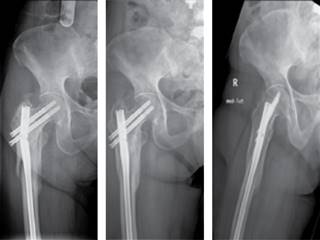

El tiempo medio de consolidación de la fractura en el grupo T2 Recon fue de 4.21 meses y de 4.09 meses para el grupo Gamma3 (Figura 1). En tres de los casos observamos un retardo de la consolidación, uno del grupo Gamma3 y dos en el grupo T2 Recon. En el caso del Gamma3 la consolidación final se dio a los seis meses tras realizar una nueva cirugía dinamizando el enclavado. Los dos casos del grupo T2 Recon presentaron un fallo por fatiga del material, se rompió el clavo en ambos casos. El primero de los casos fue un T2 Recon de 9 mm, la reducción de la fractura fue óptima, así como la posición del implante, el cual se rompió a los 4.5 meses de la cirugía. Se reintervino al paciente, se retiró el material roto y se implantó de nuevo un T2 Recon de 9 mm, dada la imposibilidad de poner un clavo de mayor diámetro por presentar un canal medular estrecho. Finalmente, la fractura consolidó a las 10 semanas (Figura 2). El segundo caso de rotura de material fue un T2 Recon de 11 mm de diámetro a los seis meses postoperatorios, se reintervino al paciente y se implantó un Gamma3 largo de 11 mm, consiguiendo la consolidación final de la fractura a las 12 semanas postoperatorias.

Figura 1: Caso clínico 1: paciente de 88 años de edad con fractura subtrocantérea tratada con clavo Gamma3 largo.